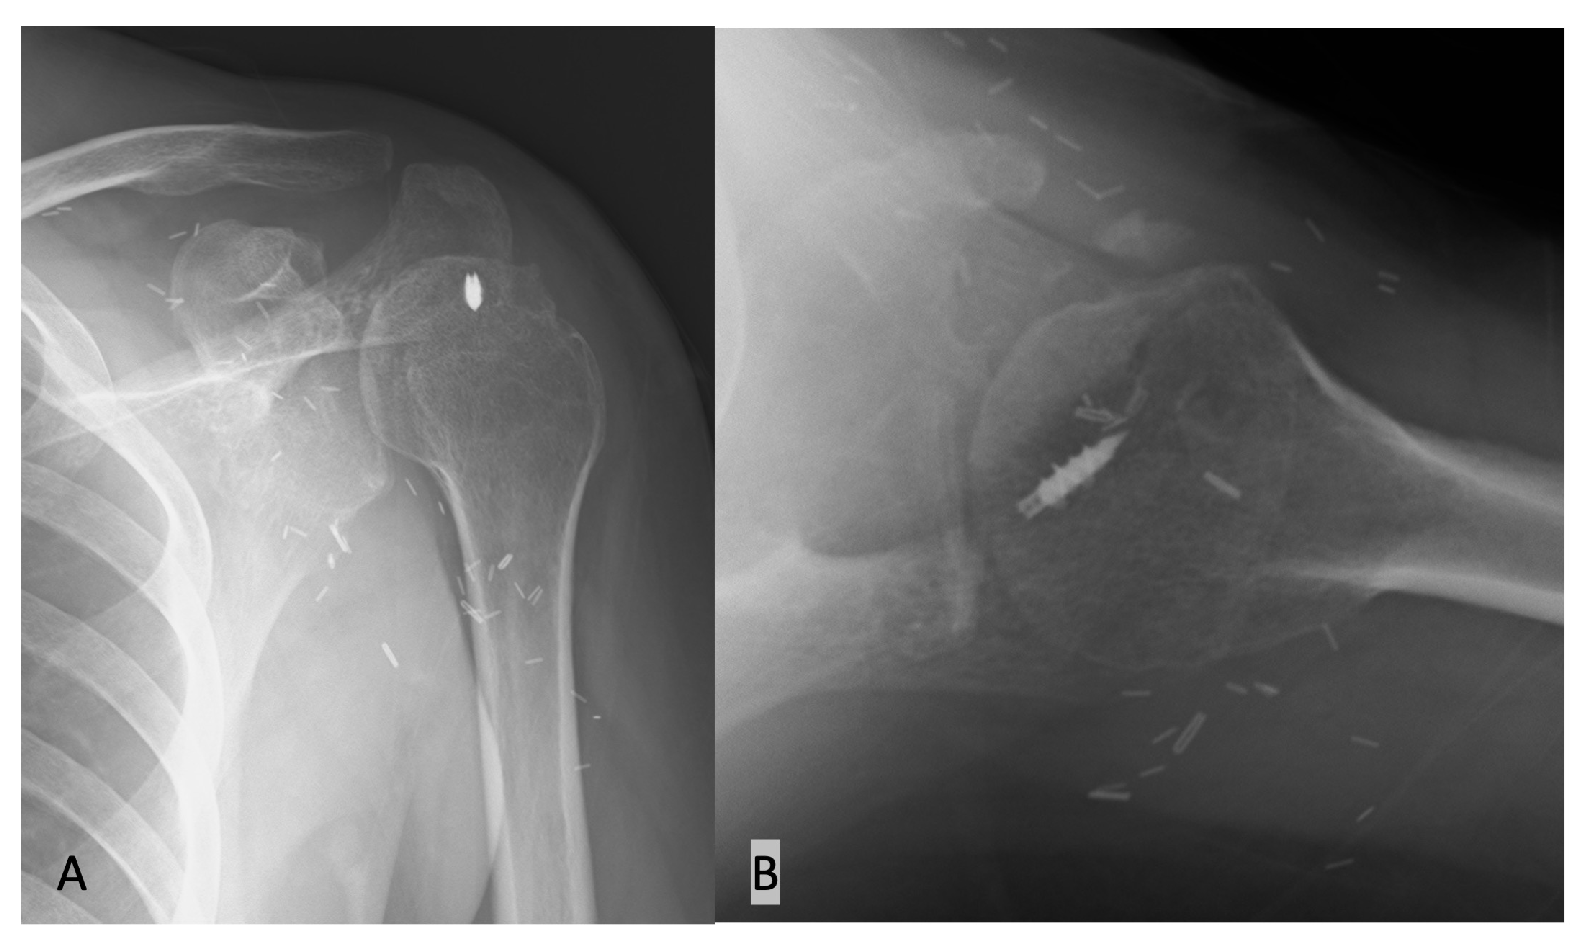

2.1. Case

2.2. Surgical Technique